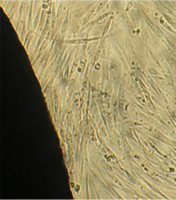

Вид монослоя и структура клеток не отличались от обычных в течение всех четырех суток наблюдения (рис. 32).

Это свидетельствует об умеренной стимуляции пролиферации фибробластов в культуре под влиянием недеминерализованной спонгиозы (таб. 9.).

Наблюдение через сутки показало, что фибробласты хорошо пристают к дну культуральной чашки, образуют равномерный монослой с плотностью 311 клеток/мм².

Фибробласты были распластаны по дну чашки, имели обычную для этих клеток удлиненную форму, 2-4 отростка, клеточная и ядерная оболочки четко контурировали.

Цитоплазма представлялась гомогенной (рис. 33). Большинство клеток имели одно центрально расположенное ядро правильной округлой формы с 1 или 2 ядрышками.